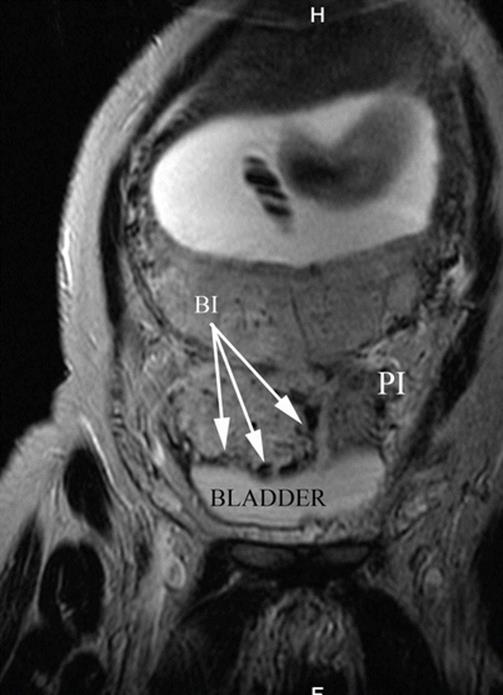

Fig. 14.13

Coronal MRI T2 image: white arrows, massive bladder invasion by AIP type 2 (percreta). Notice that placenta is lobulated. Naturally liquid contrast of bladder allows the proper identification of newly formed vessels, given their hypointense signal. PI parametrial invasion